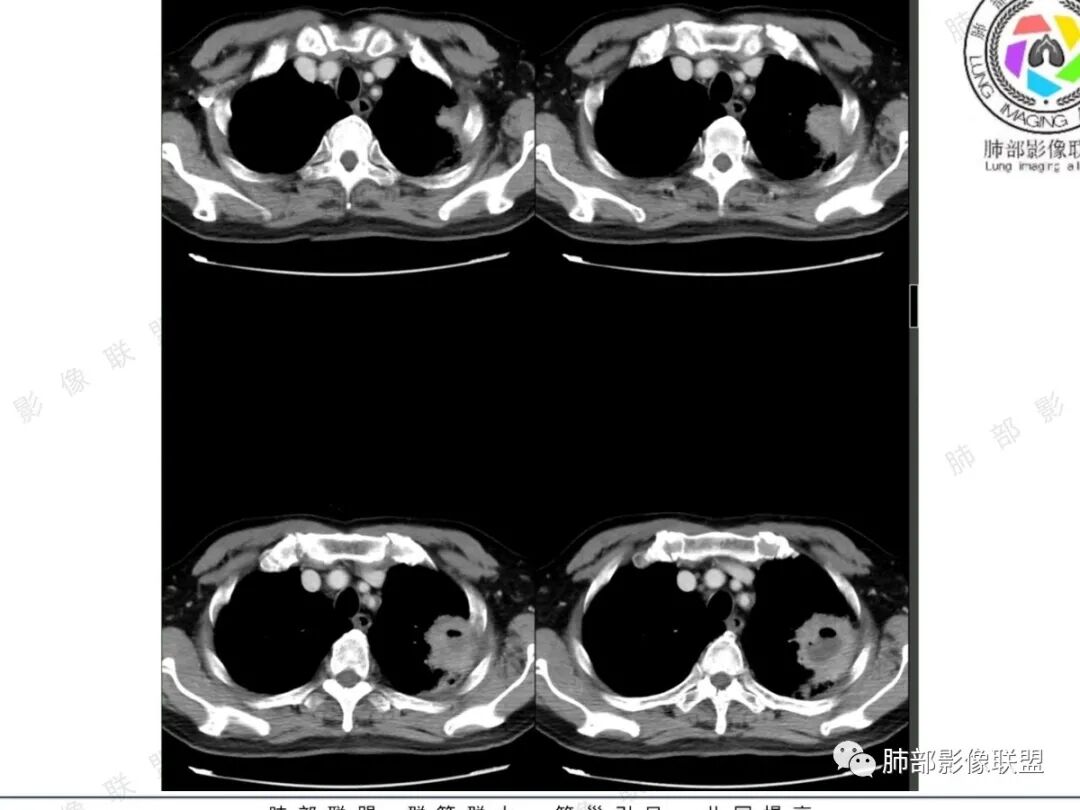

老年男性,慢性病程,左肺上叶肿块伴空洞,毛刺、浅分叶,轻中度强化,边缘斑片、小结节影,胸膜似栽赃,肿块内见液平影,考虑肺癌,鉴别肺脓肿

老年男性患者,长期的慢性咳嗽,左肺上叶胸膜下分叶状团块阴影,见有支气管截断,内部见有斑片状的坏死及小空洞影,增强扫描实质成分明显强化,坏死区未见强化  ,病灶的远端见小斑片状渗出性病变,纵隔窗纵隔内见多发肿大的淋巴结。病变的坏死区边界比较光整,空洞的内壁也比较光滑,首先考虑慢性肺脓肿,鉴别诊断应排除鳞癌或腺癌的可能。

老年男性,慢性病程,炎性指标高,左肺上叶团块影,边缘可见纤维条索,临近血管进入,支气管壁增厚,胸膜无明显栽赃,内见局灶性积气影,环形明显强化并见坏死,坏死区边界清晰,病灶周围可见少许GGO,边界尚清。考虑炎性,肺脓肿

左肺胸膜下空洞,洞壁厚薄均匀,其内可见小气泡,及低密度坏死,平扫密度均匀,增强后可见低密度坏死未强化,坏死边界清楚,空洞周围可见纤维索条,牵拉收缩,周围伴有点状小结节,考虑慢性脓肿,奴卡,放线菌,结核,鉴别肺癌性空洞(鳞癌)

左肺上叶尖后段胸膜下团块影,分叶,长毛刺,内有大片状坏死及气体影,可见气液平,周围可见条索影,明显强化,坏死区未见强化  ,病变的坏死区边界比较光整,空洞的内壁也比较光滑,邻近胸膜增厚,老年男性患者,长期的慢性咳嗽,考虑慢性肺脓肿,鉴别诊断鳞癌。

左肺上叶软组织密度肿块,局部似见栽赃,直边,边缘模糊的磨玻璃影,内见空洞及气液平,空洞内壁光滑,洞壁均匀轻中度强化,考虑良性,肺脓肿,鉴别鳞癌合并感染

左肺上叶尖后段肿块影,边缘清晰,部分平直,内密度不均,见液化坏死区及气泡影(气泡影在平扫及增强上位置有变化),增强坏死区边缘清晰,周围见斑片影及胸膜粘连肥厚。病史提及以前CT病变边缘模糊。考虑肺脓肿可能,鉴别鳞癌。

老年男性,COPD病史,咳嗽、咳痰,胸闷气喘半月,血沉升高,炎性指标不高。左肺上叶胸膜下团块状影,内有液化坏死,增强坏死边界清楚,可以环状强化影,内有明显气液平表现,支气管侧面受压,周围见片状模糊影,相邻胸膜增厚。初步诊断:慢性炎症伴肺脓肿形成。依据:环状强化+坏死边界清楚伴气液平+周围模糊影+胸膜增厚+病程半月。疑惑点,炎性指标不高,但因有抗感染治疗史,可能与用药后有关。鉴别诊断:1、鳞癌,老年男性,COPD病史,肿块中间坏死,要考虑,但坏死边界太清楚,环形强化,不是湖泊样强化,周围寸草不生,不太支持。2、肉瘤样癌,肿块中间坏死明显可以,但坏死区环形强化不支持。3、结核,病程,周围影像及强化坏死均可以,但坏死区为液性密度,不支持,结核应为干酪样坏死。4、IMT伴脓肿形成。临床和影像改变均可以。综合上,考虑慢性炎症伴脓肿形成>IMT伴脓肿形成>肺结核>鳞癌>肉瘤样癌,需要正规抗炎治疗后复查或穿刺明确。

左肺上叶团块影,边缘ggo,邻近胸膜增厚,边缘强化明显,内部见坏死区,内壁光滑,有悬浮气泡。考虑炎性病变,慢性脓肿,放线,努卡,鉴别鳞癌

左肺上叶尖后段胸膜下团块影,边缘平分叶,长毛刺,内有大片状坏死及悬浮气泡,增强坏死边界清晰,壁均匀渐进性强化,周围肺野可见长条索及斑片影,邻近胸膜增厚,老年男性,慢阻肺病史,考虑肺脓肿?放线菌?鉴别恶性肿瘤病变!

左肺上叶胸膜下肿块,良恶性征象都有,强化后坏死区内可见分隔,坏死区内可见悬浮气泡,坏死边界清新,光滑,肿块周围散模糊的GGO,空洞壁内可见支气管穿行,病灶整体沿支气管分布,未见明显支气管截断征,近端支气管壁增厚,强化部分明显均匀,胸壁未见侵犯征象,以上都是良性征象,但是主动脉弓前可见淋巴结肿大,用炎性解释感觉比较纠结,考虑炎性病变(慢性脓肿、IMT、放线菌),鉴别腺癌或者肉瘤样癌、癌肉瘤

看影像

周围ggo

细长毛刺

边缘平直,收缩,没有膨隆

厚壁空洞,内壁光滑,内部液化坏死

厚壁环形强化明显

有气泡

考虑慢性脓肿形成

鳞癌,老年男性支持,影像不太支持,空洞壁光整,没有壁结节,坏死太彻底,鳞癌湖泊样坏死有过渡区。

结核,周围太干净,没有树芽,钙化,增殖灶。结核应为干酪样坏死。